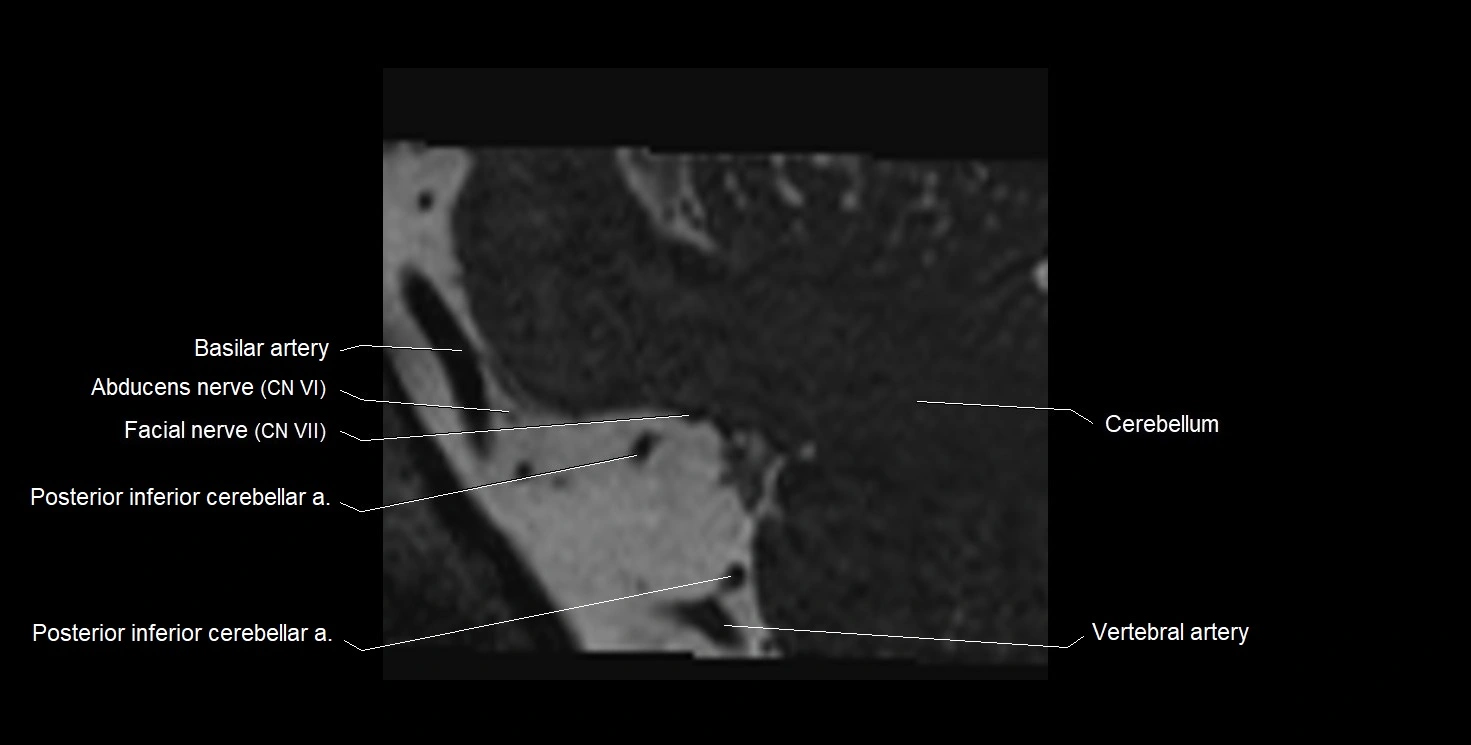

MRI Appearance

• The abducens nerve is a small, thin, linear structure

• Best visualized on high-resolution T2-weighted 3D MRI sequences (e.g., FIESTA or CISS)

• Seen as a hypointense (dark) line running from the brainstem at the pontomedullary junction, traversing the prepontine cistern, and entering Dorello’s canal under the petrosphenoidal ligament, then into the cavernous sinus, and finally the orbit

• May be challenging to visualize in standard MRI due to its small size

• Pathology may be inferred by absence, displacement, or enhancement of the nerve